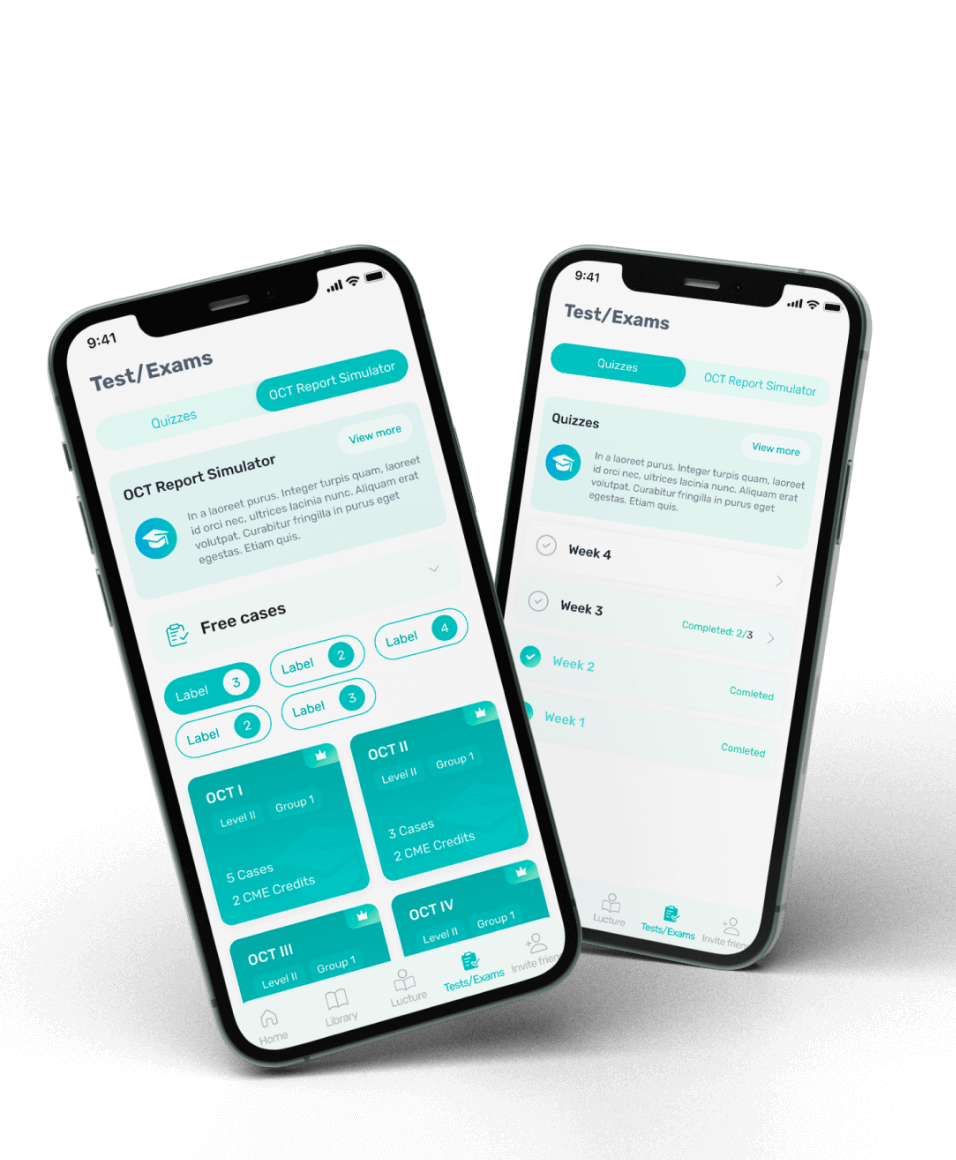

An innovative web and mobile app for Optical Coherence Tomography interpretation.